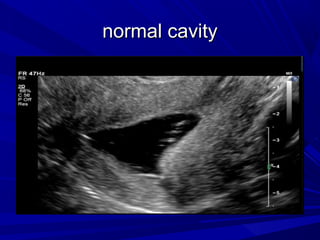

normal cavity